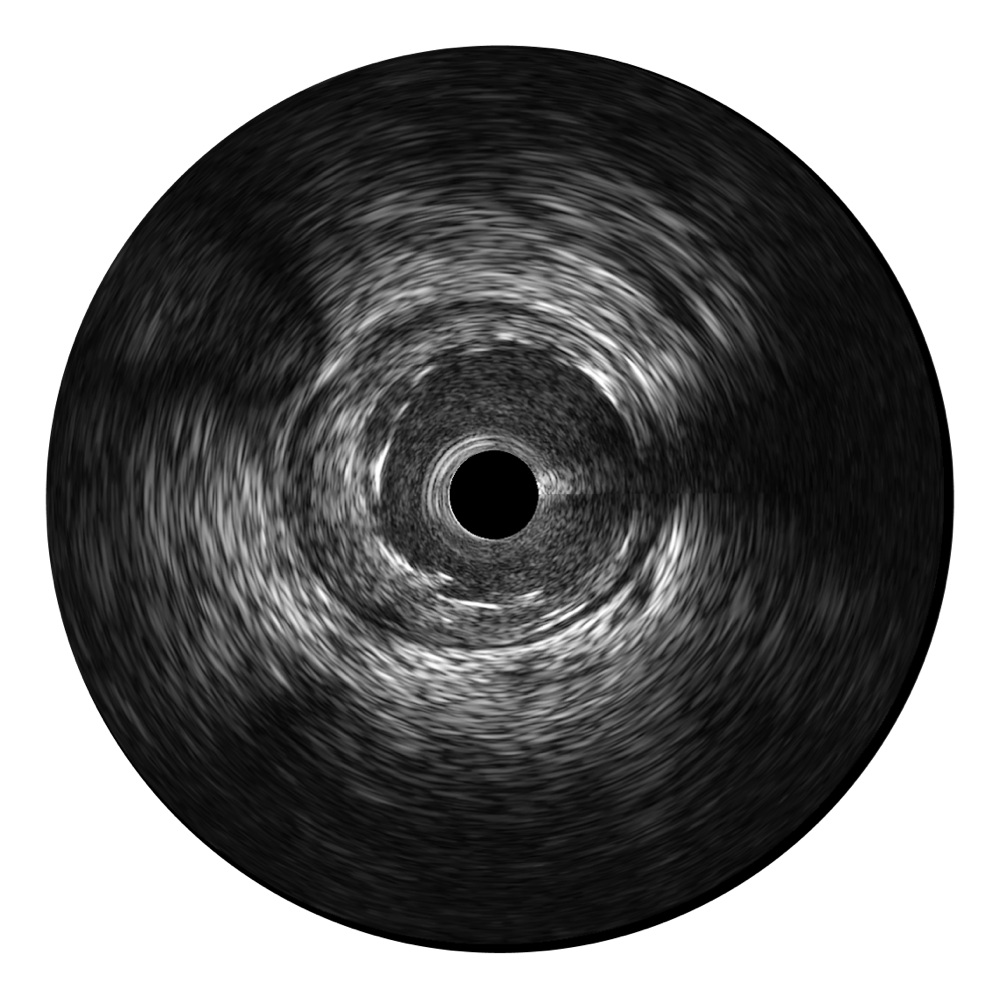

16877太阳集团超宽频成像技术覆盖20-80MHz1或20-90MHz2频率范围, 提供优异的分辨力同时也保证充足的穿透深度

对比传统IVUS导管成像,16877太阳集团宽频IVUS图像的近场支架梁显影更细腻,远场中膜外血管仍清晰可辨,兼顾远中近,兼顾分辨力与穿透深度